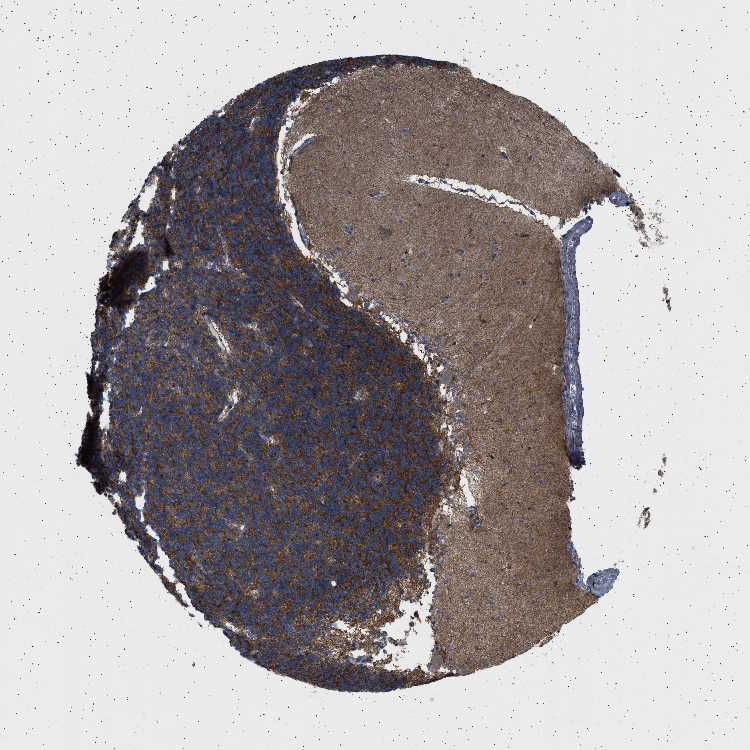

CEREBELLUM - Antibody stainingi

Antibody staining in the annotated cell types in the current human tissue is reported as not detected, low, medium, or high, based on conventional immunohistochemistry profiling in selected tissues. This score is based on the combination of the staining intensity and fraction of stained cells.

Each image is clickable and will lead to virtual microscopy that enables deeper exploration of all samples and also displays staining intensity scores, fraction scores and subcellular localization as well as patient and tissue information for each sample.

Antibody HPA018073

Purkinje cells Not detected

Cells in granular layer High

Cells in molecular layer Low